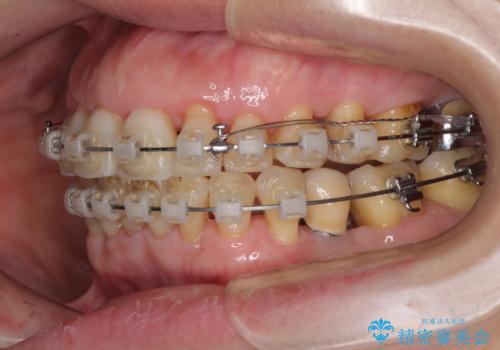

- 矯正装置

- クリアブラケット

- 治療期間

- 2年

- 治療回数

- 10-30回